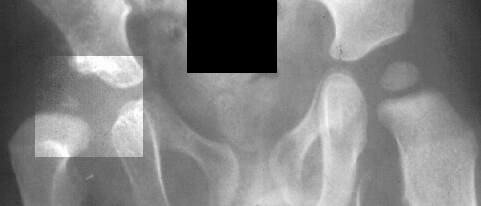

X-rays

and

arthrogram at two years of age show irregular ossification of the femoral

head and dysplastic acetabulum,

but the hip coverage was acceptable even in adduction.